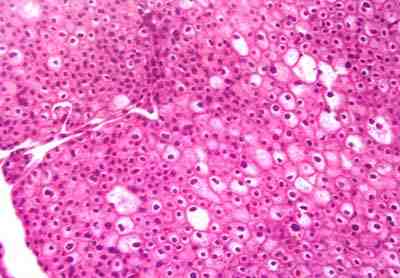

Micro: Se observa células acidofílicas pálidas, con reforzamiento de la membrana citoplasmática, en su mayoría, con citoplasma de aspecto espumoso, núcleos centrales o ligeramente excéntricos, hipercromáticos y halo claro perinuclear.

Anatomía patológica concluye:

NEOPLASIA EPITELIAL MALIGNA: CARCINOMA RENAL CROMÓFOBO. Actualmente la paciente se encuentra en buenas condiciones, con controles periódicos.